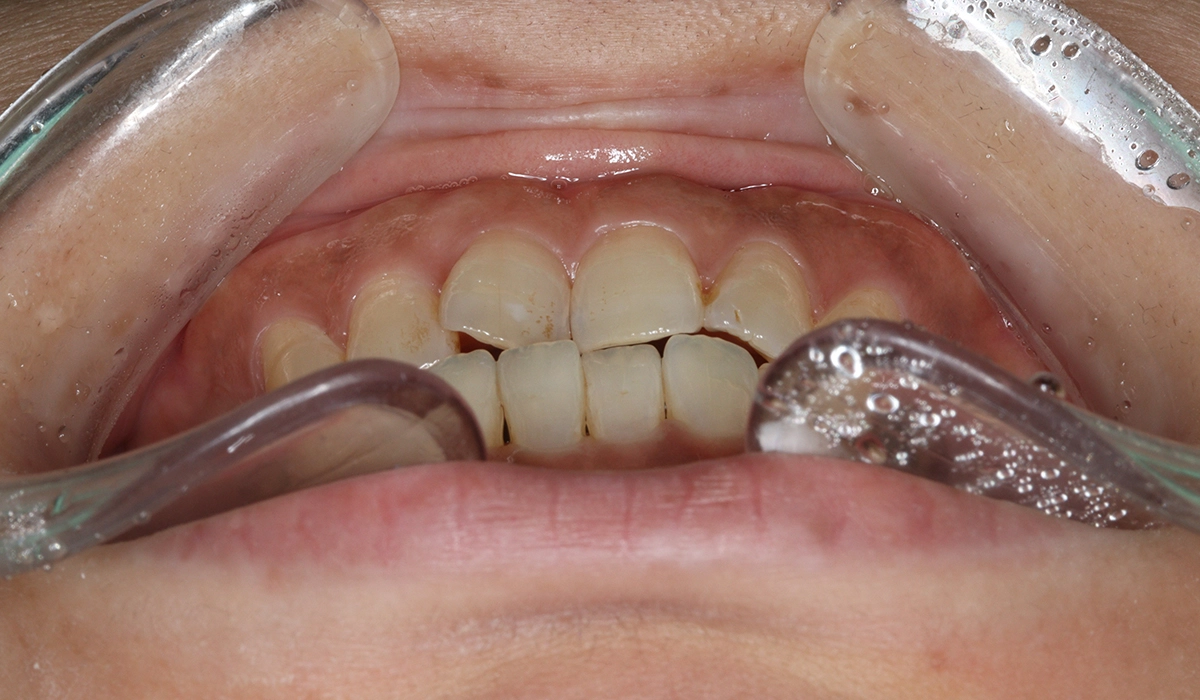

術後:正面